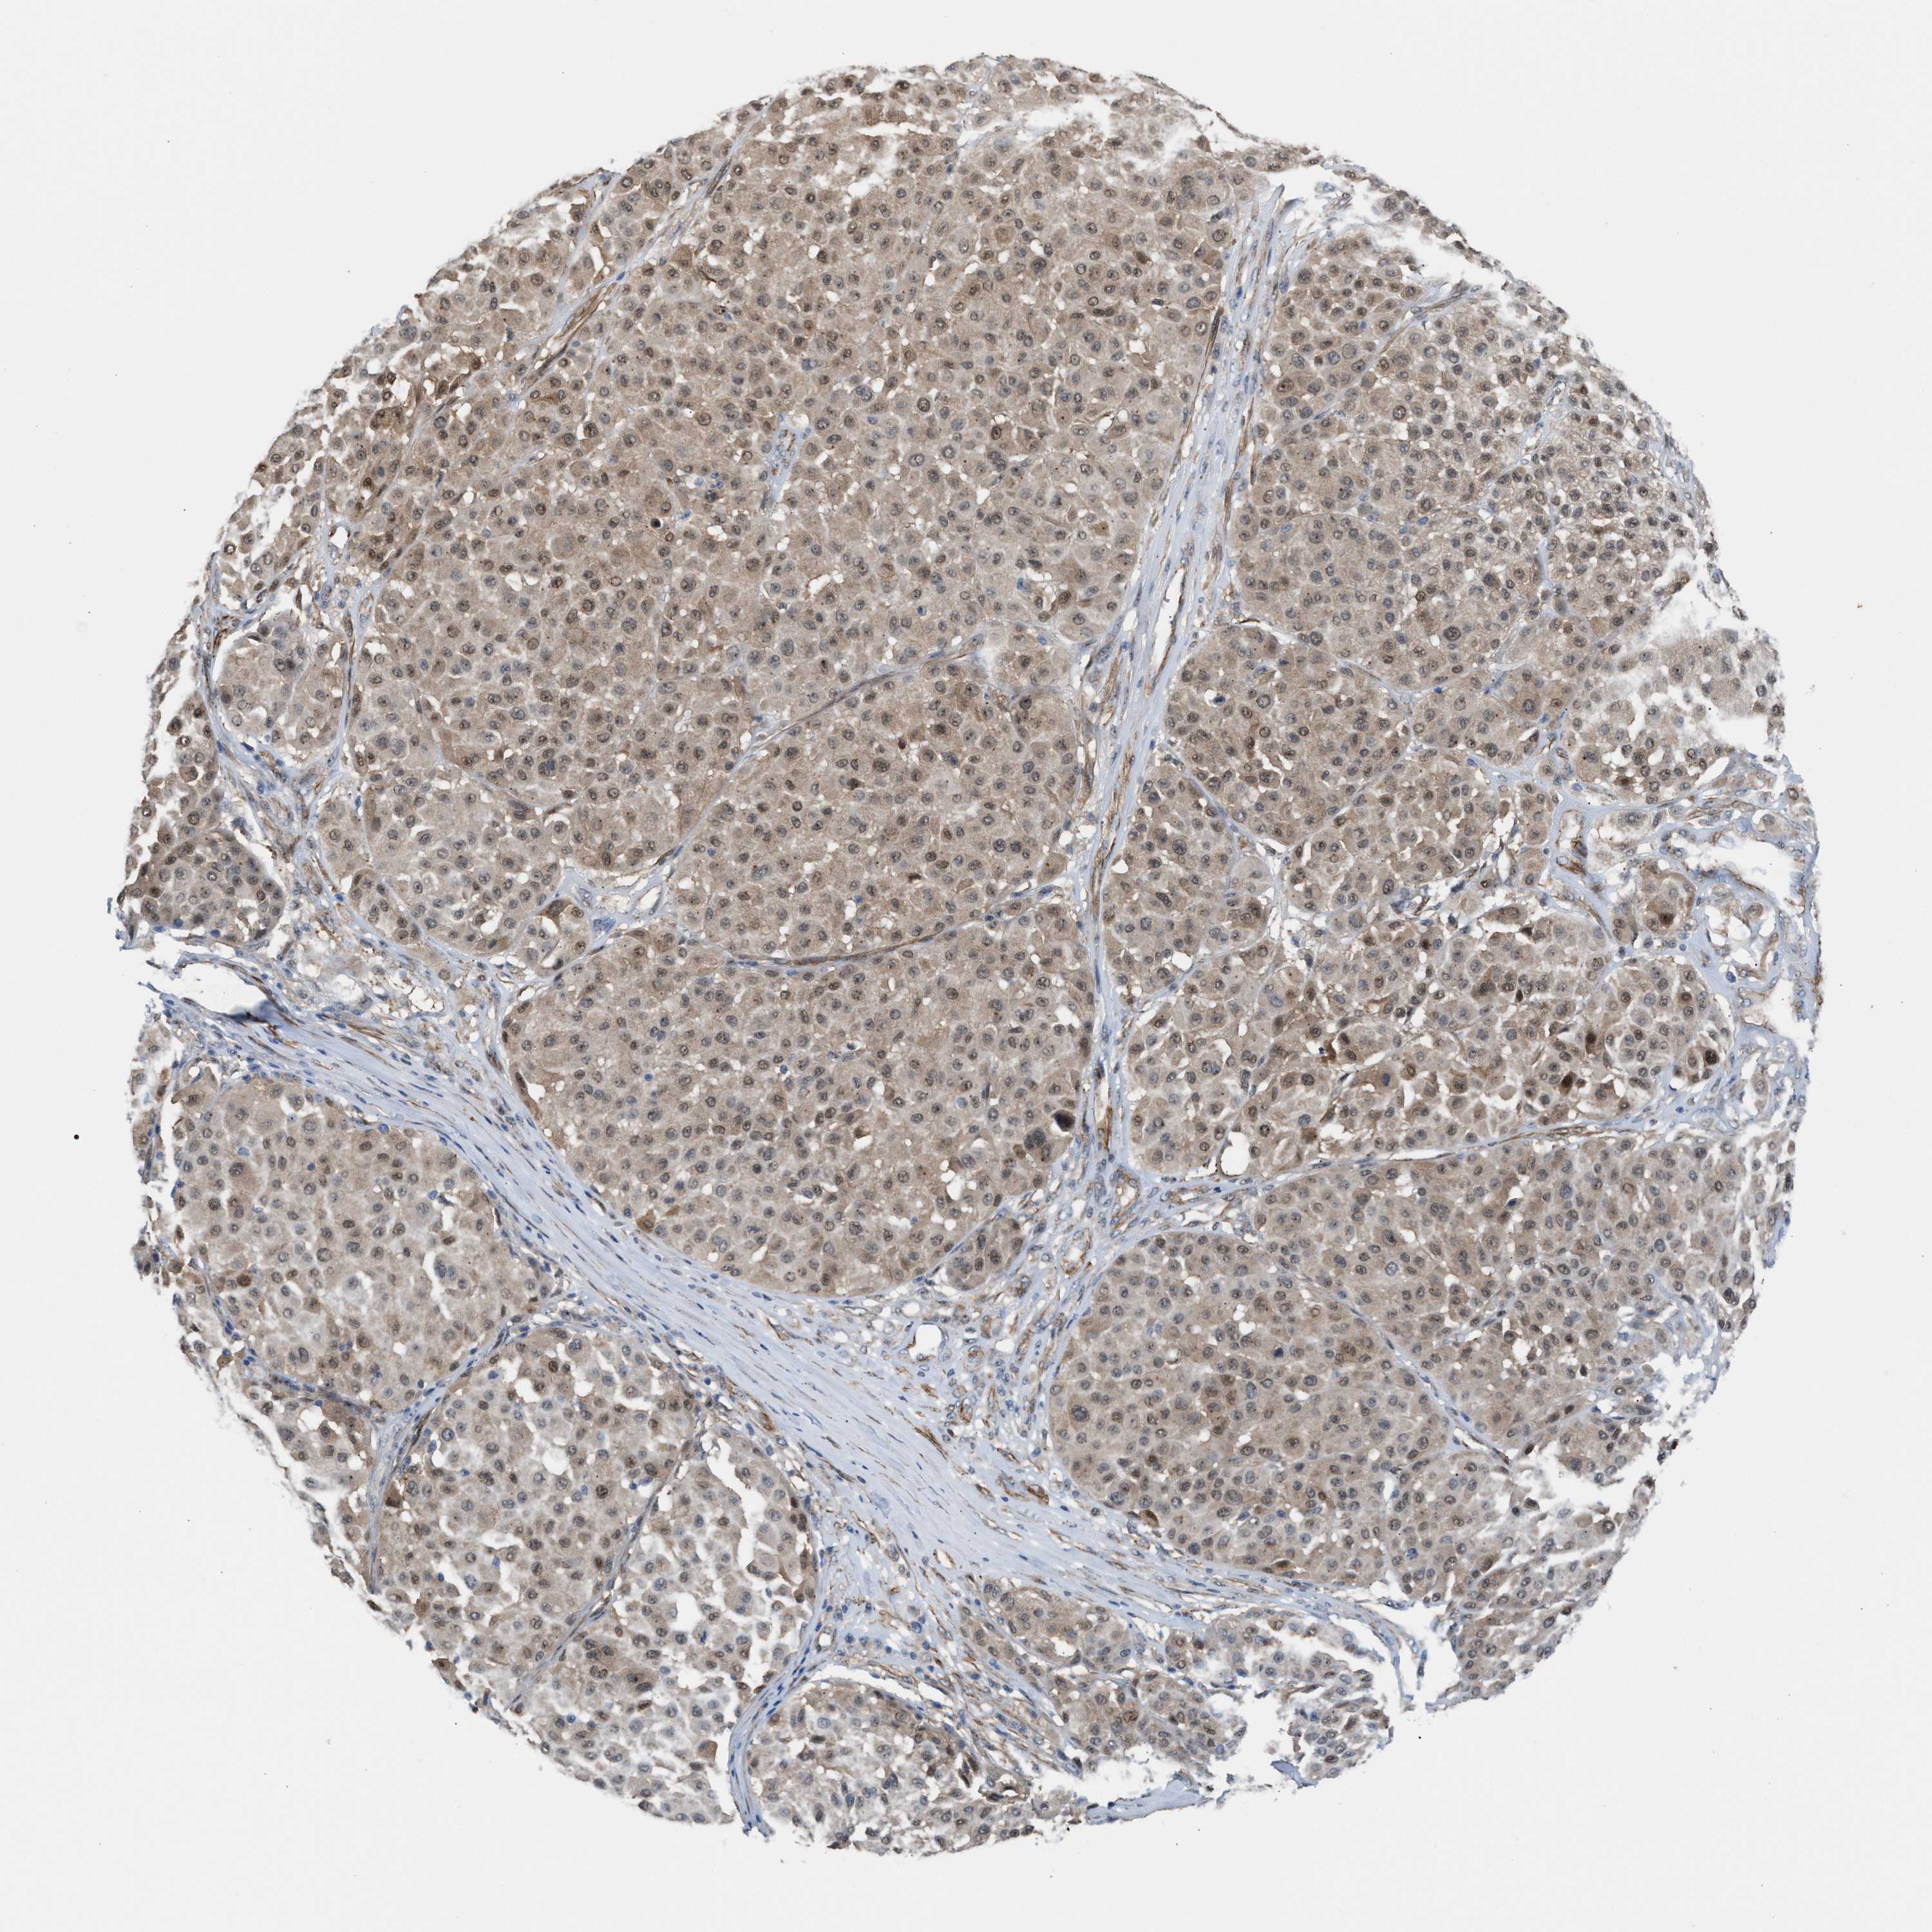

MELANOMA - Protein expressioni

A mouse-over function shows sample information and annotation data. Click on an image to view it in a full screen mode. Samples can be filtered based on level of antibody staining by selecting one or several of the following categories: high, medium, low and not detected. The assay and annotation is described here.

Note that samples used for immunohistochemistry by the Human Protein Atlas do not correspond to samples in the TCGA dataset.

Antibody stainingi

Antibody staining in the annotated cell types in the current human tissue is reported as not detected, low, medium, or high, based on conventional immunohistochemistry profiling in selected tissues. This score is based on the combination of the staining intensity and fraction of stained cells.

Each image is clickable and will lead to virtual microscopy that enables deeper exploration of all samples and also displays staining intensity scores, fraction scores and subcellular localization as well as patient and tissue information for each sample.

Antibody HPA021283

Antibody HPA021332

Staining

High

Medium

Low

Not detected

Intensity

Strong

Moderate

Weak

Negative

Quantity

>75%

75%-25%

<25%

None

Location

Nuclear

Cytoplasmic/membranous

Cytoplasmic/membranous,nuclear

Malignant melanoma, NOS